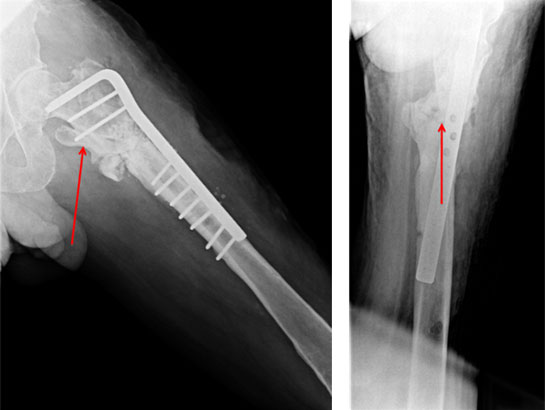

| The arrows show calcium sulfate pellets loaded with antibiotic. These pellets help in the elution of high dose of antibiotic locally to the infected area. This helps in better control of infection and obviates the need to give intravenous antibiotics for a long time (recommended period in osteomyelitis is 4-6 weeks of IV antibiotics). The advantage of using the calcium sulfate pellets is that it gets completely absorbed in around 6 weeks time, thereby preventing the need for another surgery. | ||